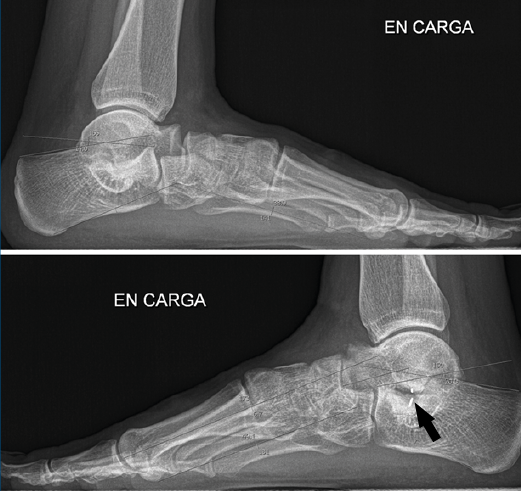

Primer caso (Figura 6)

Se trata de una paciente mujer de 27 años de edad, auxiliar sanitaria, con antecedentes de asma, depresión y psoriasis, que presenta un pie izquierdo plano valgo doloroso de 24° de valgo talar, por sinostosis calcaneoastragalina posterior. Dicha paciente presentaba una clínica de dolor en el seno del tarso y los tendones peroneos laterales. Como pruebas complementarias, se realizaron radiografías en carga de los pies y los tobillos, TAC y RMN del tobillo afecto. Se diagnostica de coalición tarsal de tipo 3 de la clasificación de Rozansky(26). Las articulaciones tibioperoneoastragalina y subtalar están preservadas clínica y radiológicamente. El balance articular es de: flexión = 45°; extensión = 15°; inversión = 5°; eversión = 0°. La escala de la American Orthopaedic Foot and Ankle Society (AOFAS) para el tobillo izquierdo presentaba un valor de 60 (20-35-5). Los ángulos radiológicos iniciales son: Moreau-Costa-Bartani interno = 143°; declinación talar = 25,8°; Meary = 9,9°; Kite = 25,5°; taloescafoideo = 54,6° (Tabla 1).